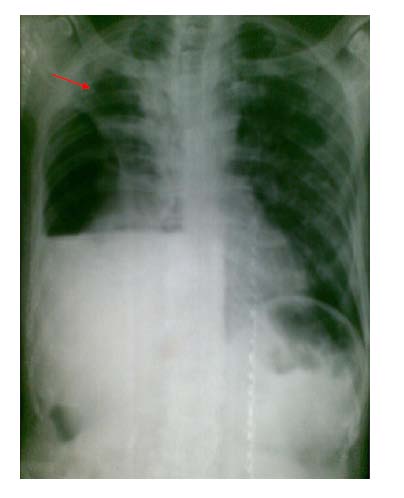

Please note that in this x ray (figure 12 ) the outline of the collapsed lung margin on the right side is very faint.

This is an example of localized apical pneumothorax. A prominent cardiomegaly and a prominent medial border of the scapula on the left side is two distracting features in this x ray.

In figure 13 we can see close up view of the localized apical pneumothorax. Please observe that free air in the pleural cavity (pneumothorax) is situated between the two (visceral and parietal) layers of pleura. The visceral layer outlines the outer border of the collapsed lung.